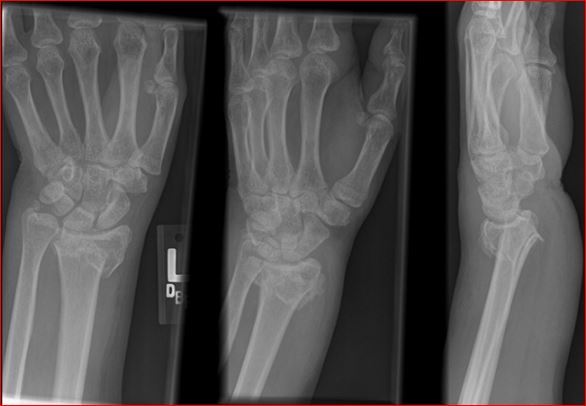

Shows distal radius fracture with shortening and dorsal displacment.

This injury is known as Colles’ fracture.

Ulnar styloid fracture, scaphoid fracture and acute carpal tunnel syndrome

Management of Distal Colles fracture

Most can be managed with conservative measures such as sugar tong splinting, with or without closed reduction.

More severe injuries, especially those with significant displacement or angulation >15-20 degrees may require urgent orthopedic consultation for possible surgical intervention